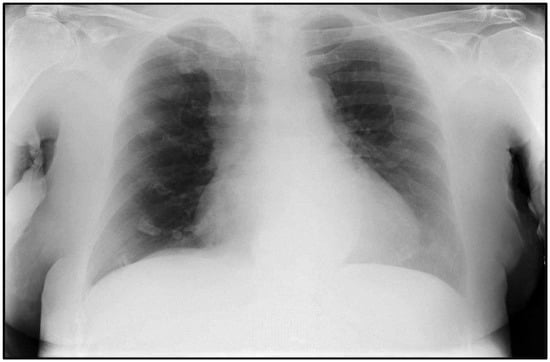

2.2. Case #2